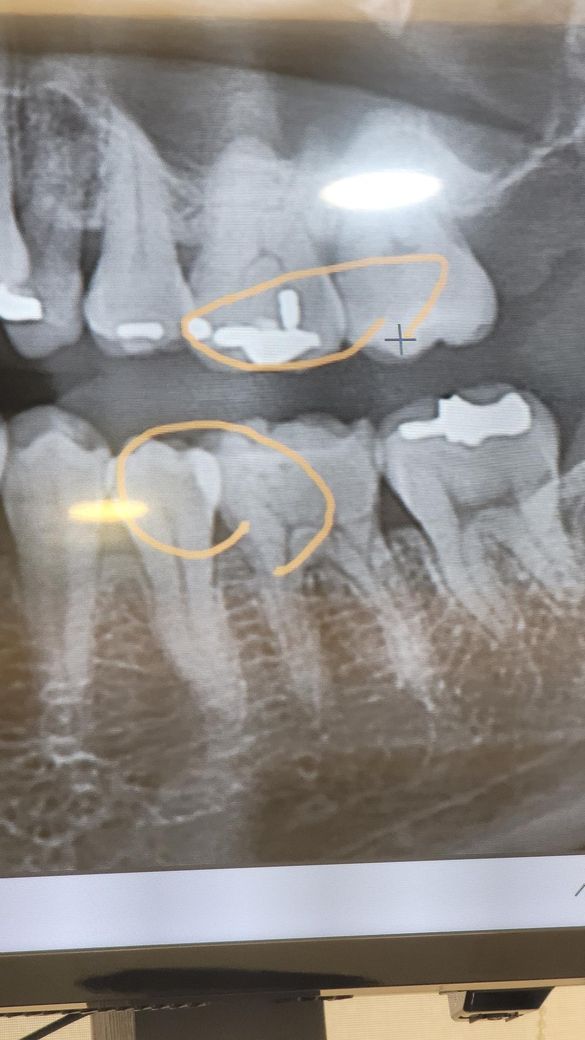

밑에 동그라미 친 어금니 왼쪽 이 충치가 생겻는데요 거의 인접면 충치 처럼 거의 끝자락에 났습니다 그렇다고 인접면 충치는 아니고요 근데 엑스레이로 볼땐 충치가 아닌것 같은데.. 치료는 하기는 했거든요 어떠신가요??

• 1번 째 사진